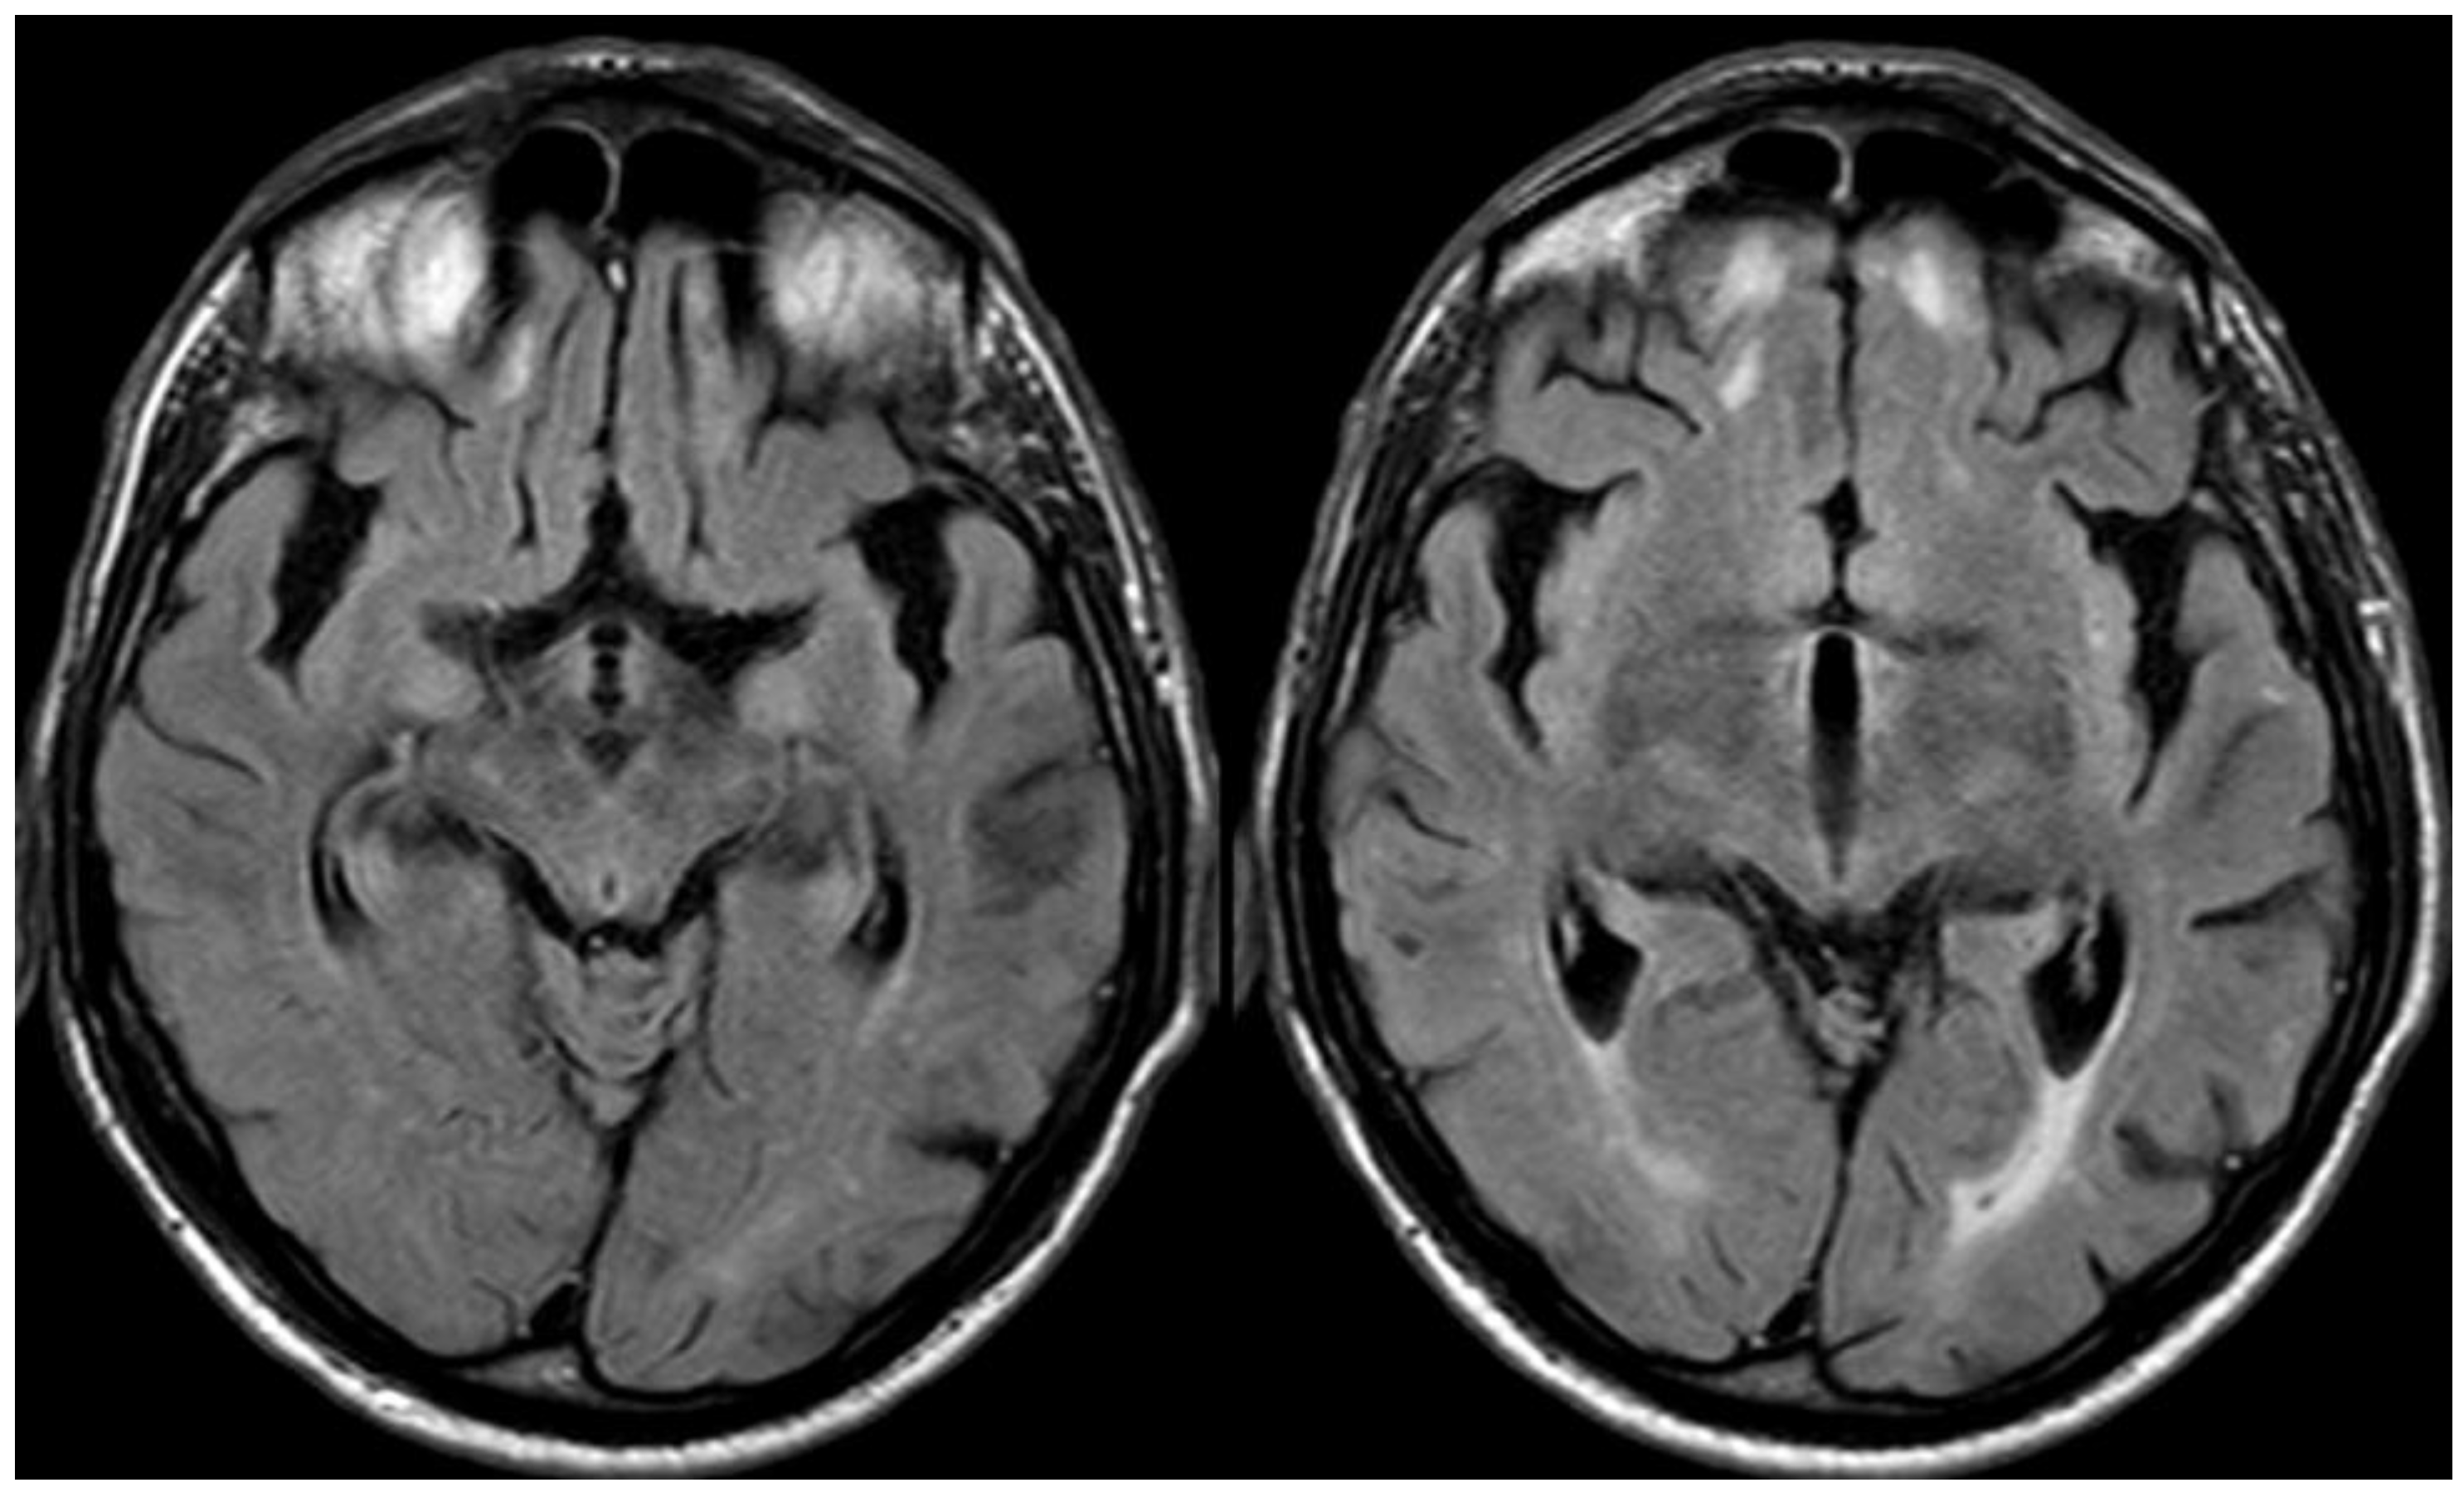

3. May 2014: CAA-Related Inflammation

5. February 2017: First Recurrent CAA-Related Inflammation

7. April 2018: Second Recurrent CAA-Related Inflammation